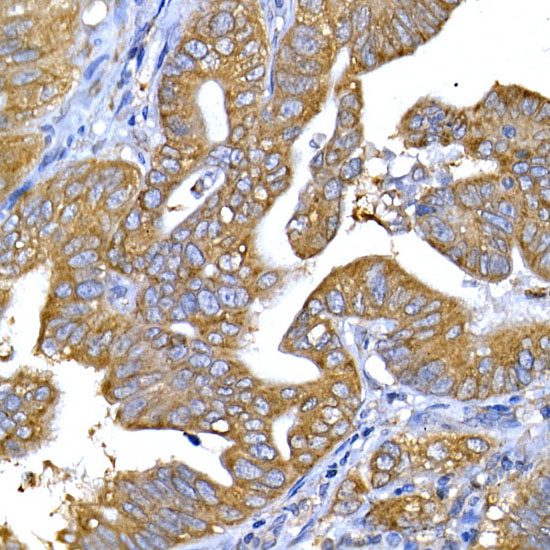

Immunohistochemistry analysis of paraffin-embedded Human lung cancer tissue using IRS-1 Antibody.